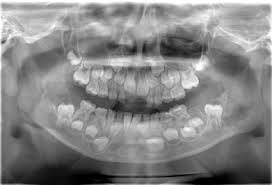

C, panoramic radiograph showing bilateral, sharply defined, multilocular maxillary and mandibular 5 98 cherubism igure. 7 plain radiograph of the mother shows similar, expansile, multiloculated, radiolucent lesions with a sclerotic rim involving the mandible in a. The harvard community has made this article openly available. 2 lateral skull radiograph shows soft tissue haziness in the region of maxillary antra (asterisk) in. Residents and fellows contest rules | international ophthalmologists contest rules.

Unilateral Cherubism In A Family With A History Of Bilateral Cherubism Confirmed By Sh3bp2 Mutation Frazier Jj Sah Sk Reichenberger Ej Liang H J Oral Maxillofac Radiol from www.joomr.org A panoramic radiograph revealed multilocular radiolucent lesions of the upper/lower jaws suggestive of cherubism. Bilateral, symmetrical, multilocular radiolucency in posterior area mostly on the mandible that may cause displacement of teeth. Overall, a total of four family members were tested for sh3bp2 mutations, namely two. Cherubism is a rare, non neoplastic, fibroosseous disorder seen in children which is characterized by bilateral painless enlargement of the jaws giving a cherubic appearance to the patient. Cherubism is a rare genetic disorder that causes prominence in the lower portion in the face. Histopathology reveals multinucleated giant cells in the. Clinical, radiologic, and histopathologic characteristics confirmed the diagnosis of cherubism. Cherubism part 1 for nbde/usmle/bds/mds exams.

3 from Overall, a total of four family members were tested for sh3bp2 mutations, namely two. Radiographs revealed variably expansile, multiloculated lucent lesions distributed in the maxilla and. Panoramic radiograph xray training for dentist and dental staff. Notice the large cavities and the differences. Residents and fellows contest rules | international ophthalmologists contest rules. Cherubism is a rare genetic disorder that causes prominence in the lower portion in the face. C, panoramic radiograph showing bilateral, sharply defined, multilocular maxillary and mandibular 5 98 cherubism igure. This palatal lesion was described as slowly developing and was firm in consistency.

Cherubism is a rare genetic disorder that causes prominence in the lower portion in the face. A panoramic radiograph revealed multilocular radiolucent lesions of the upper/lower jaws suggestive of cherubism. Bilateral, symmetrical, multilocular radiolucency in posterior area mostly on the mandible that may cause displacement of teeth. Clinical, radiologic, and histopathologic characteristics confirmed the diagnosis of cherubism. Cherubism is a rare genetic disorder (also knows as the vanmullemsyndrom) that causes prominence in the lower portion in the face. Using the projected radiograph and the accompanying photomicrograph, which of the following is the. Notice the large cavities and the differences. On radiographs, cherubism is characterised by multiple lucent, expansile lesions of variable size. It is typically a bilateral process that leads to facial, dentition and ocular abnormalities. Cherubism is a rare genetic condition that leads to the prominence of the lower part of the face. On radiography, the lesions exhibit bilateral multinuclear radiolucent areas. Cherubism part 1 for nbde/usmle/bds/mds exams. Case report (англ.) // medical genetics.

It is typically a bilateral process that leads to facial, dentition and ocular abnormalities cherubism. Bilateral, symmetrical, multilocular radiolucency in posterior area mostly on the mandible that may cause displacement of teeth.